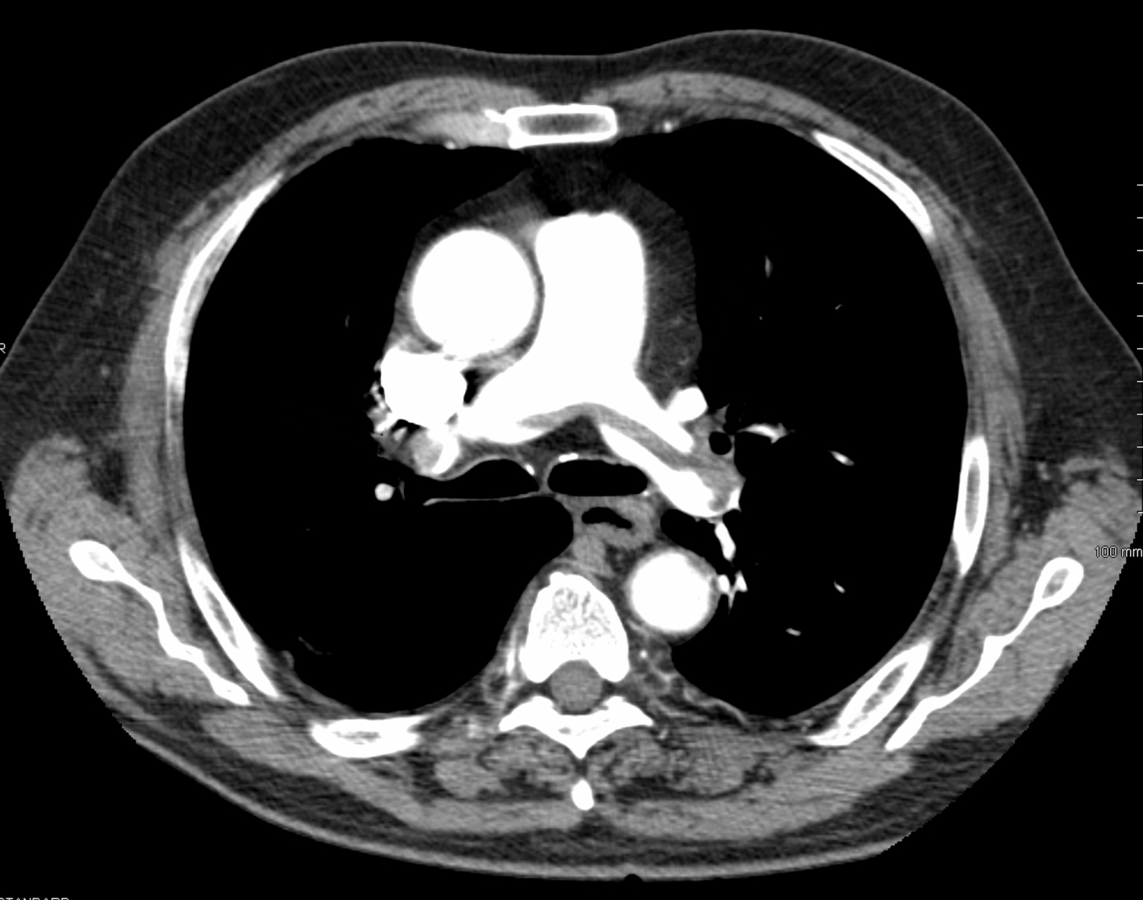

Nach einer Lungen­embolie heißt es: spritzen, spritzen, spritzen. Nach einer Lungen­embolie heißt es: spritzen, spritzen, spritzen. © wikipedia/James Heilman

Eine erstmalige tiefe Venenthrombose oder eine Lungenembolie, v.a. wenn sie ohne Auslöser wie längere Bettlägerigkeit aufritt, kann der erste Hinweis auf ein Malignom sein. Soll man alle diese Patienten ohne Unterschied durch CT/MRT/SPECT schicken? Das scheint bei der Tumordiagnose eher keinen Nutzen zu haben und den Patienten unnötig zu verschrecken, wie mehrere Studien herausfanden. Demnach gilt: Patienten beruhigen, ihn untersuchen, Laborwerte bestimmen (Blutbild, Kalzium, Leberwerte, Urinstatus), Röntgen-Thorax veranlassen und die üblichen adäquaten Screening-Maßnahmen (z.B. auf Mamma-, Zervix-, Kolon-, Prostata-Karzinom).

Lungenembolie Lungenembolie © wikipedia/James Heilman